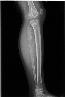

胫骨尤因肉瘤

病史: 入院情况:因“反复左小腿疼痛3年,发现左小腿肿胀2月”入院。查体:左小腿中上段可扪及约10cm*8cm*8cm大小包块,皮肤完整,无发红,局部皮温增高,包块表面皮肤欠光滑,质地硬,边界不清,无..

诊断与讨论: 左小腿中上段尤文氏肉瘤

分类: 骨骼与肌肉系统骨肿瘤与肿瘤样病变尤文氏肉瘤